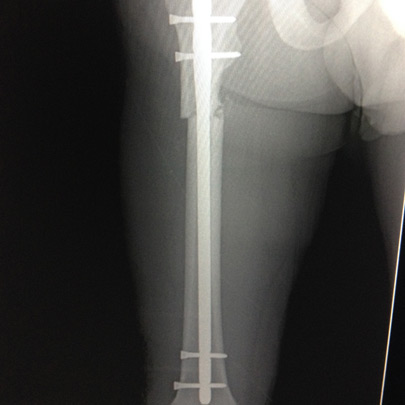

Fracturas y luxaciones

Tratamientos quirúrgicos